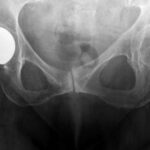

Οστεοαρθρίτιδα του ισχίου

Τι είναι η οστεοαρθρίτιδα του ισχίου; Η οστεοαρθρίτιδα του ισχίου είναι μία πάθηση, κατά την οποία επέρχεται φθορά του αρθρικού χόνδρου του ισχίου. Προκαλείται συνήθως από πολλές παθήσεις που δημιουργούν…